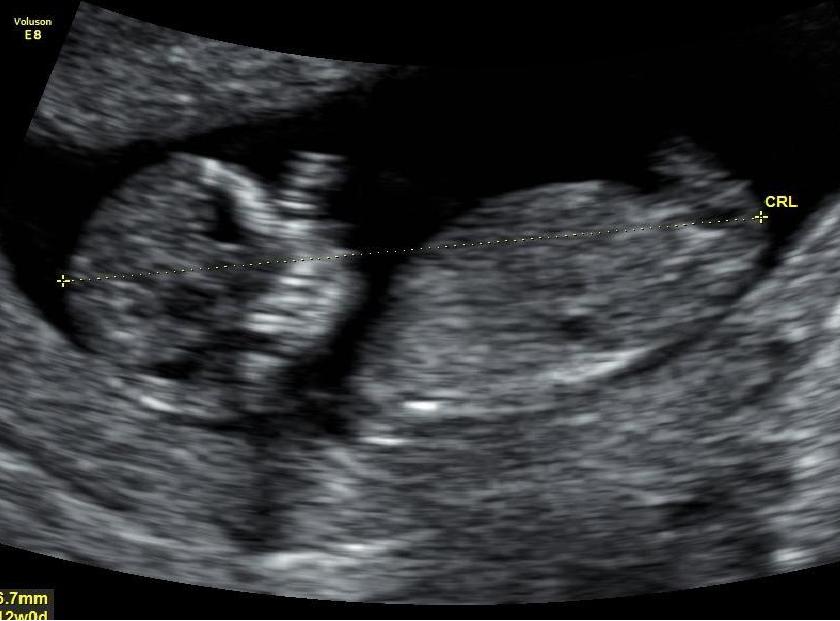

Anyone feel confident to guess my babys 12 week ultrasound please?????Attachment 17236Attachment 17237

My guess is boy based on top picture but it's just a guess.

It's not a very clear picture, but I will go with girl. I'm not sure if what I can see is a nub or not. If it is, then girl.